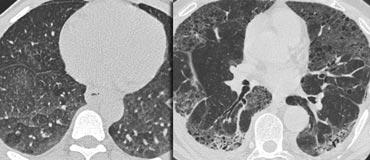

LEFT: No fibrosis, so potentially treatable lung disease. RIGHT: Fibrosis, so no treatable lung disease.

Có thể điều trị hay không thể điều trị?

Mặc dù GGO không đặc hiệu, đây là một dấu hiệu có ý nghĩa quan trọng: 60–80% bệnh nhân có GGO trên HRCT mắc bệnh phổi đang hoạt động và có khả năng điều trị được.

Trong 20–40% trường hợp còn lại, GGO phản ánh tình trạng xơ hóa và bệnh không thể điều trị được.

Trong những trường hợp này, các dấu hiệu xơ hóa đi kèm trên HRCT thường hiện diện, chẳng hạn như giãn phế quản do co kéo và tổ ong.

Ví dụ

Các hình ảnh cho thấy hai trường hợp có GGO: một trường hợp không có xơ hóa (có khả năng điều trị được) và một trường hợp có giãn phế quản do co kéo (cho thấy có xơ hóa).